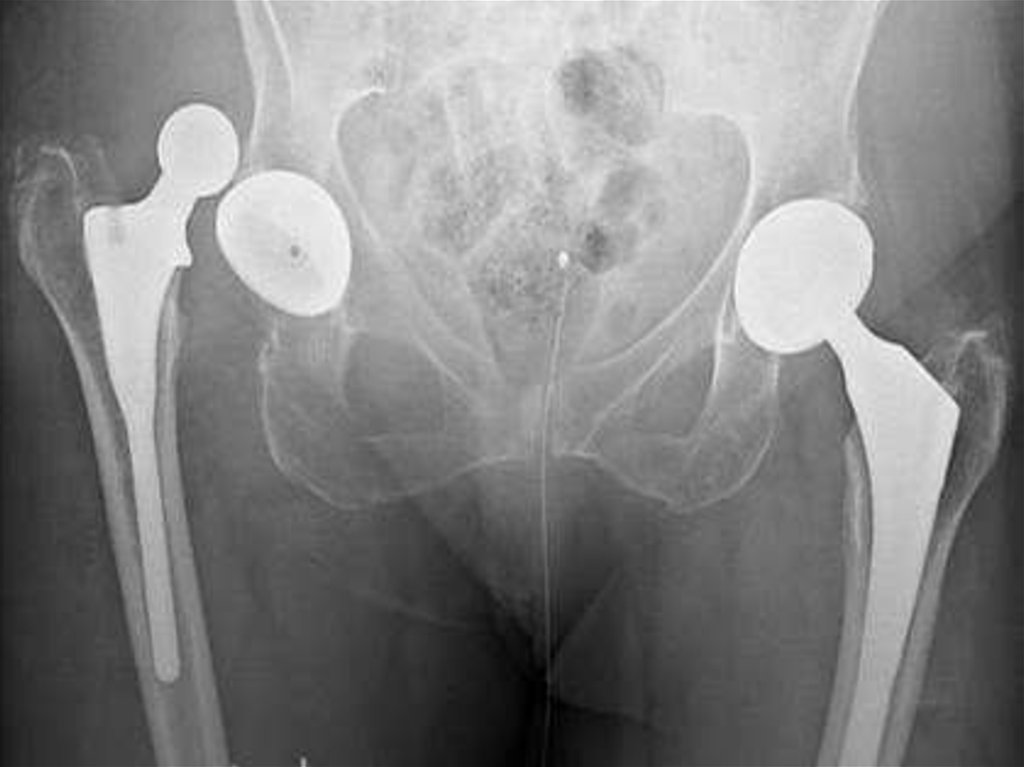

1.Кистовидная перестройка головки бедра и вертлужной впадины

при диспластическом коксартрозе

2.Краевое разрастание (остеофиты)